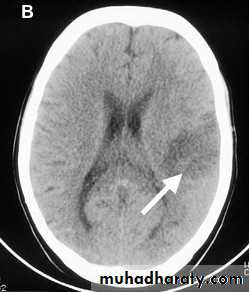

Established infarction (days to weeks after onset) (Figure 1b) - the CT changes are more obvious:

The infarcted area looks dark - the older the darker

Cortical infarcts are typically wedge shaped

Lacunar infarcts look like small black holes. They measure less than 1 cm in diameter and are located subcortically, usually in the basal ganglia or internal capsule.

Figure 1b: Established infarct (some days old) in the left middle cerebral artery territory.